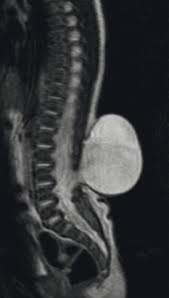

meningocele

semi severe form of spina bifida; meninges protrude thru the undeveloped opening

myelomeningocele

most severe form of spina bifida where meninges and spinal cord protrude through the opening